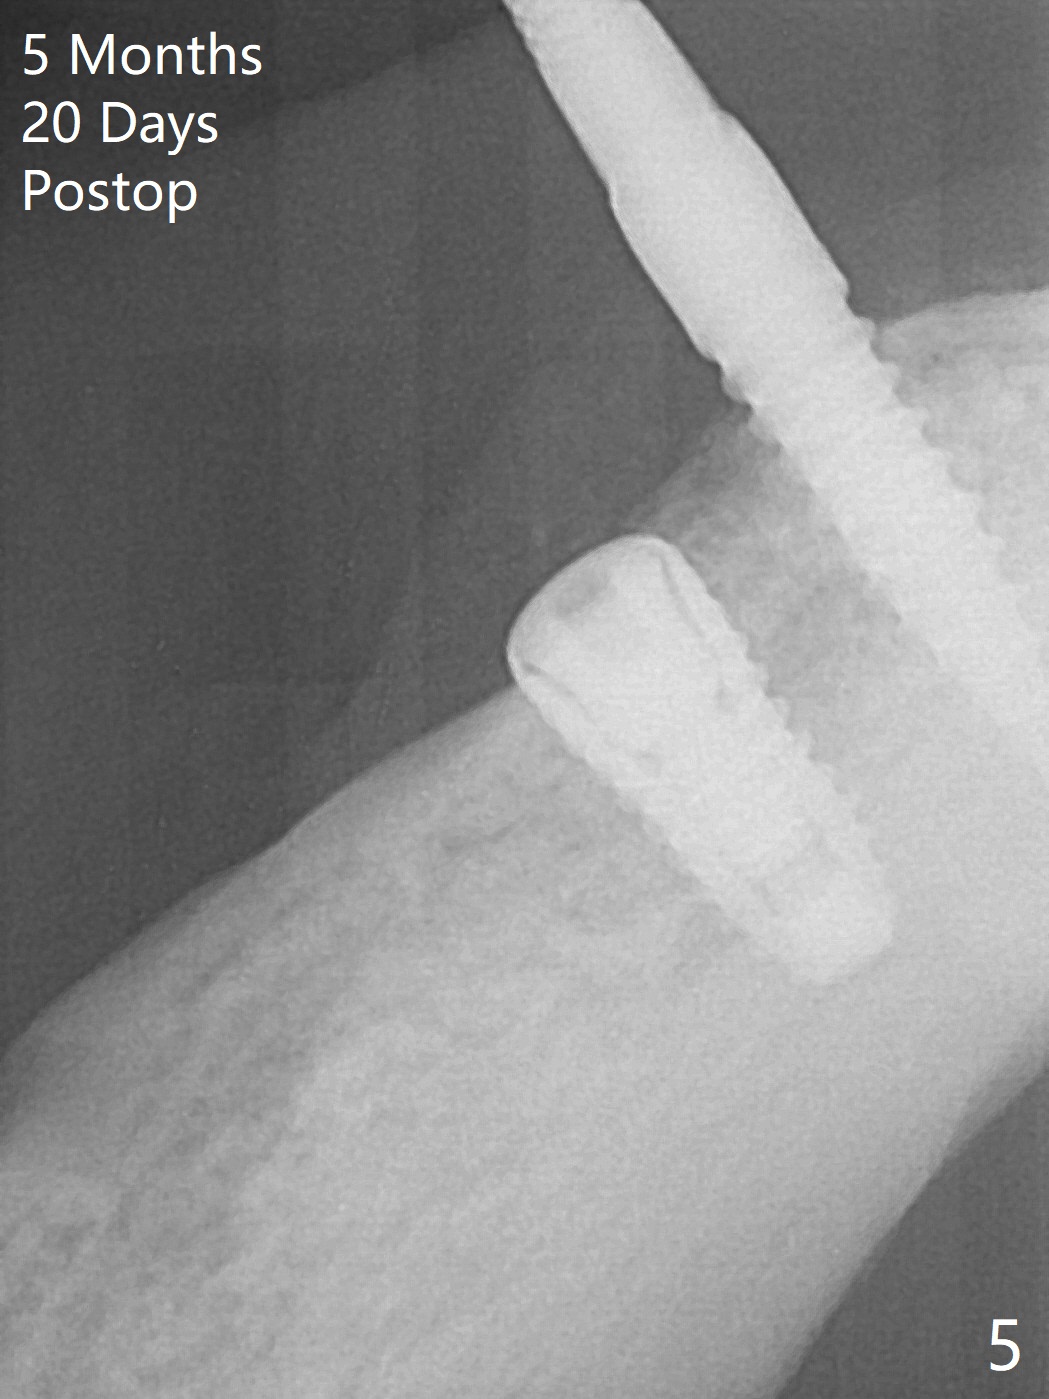

Two months post removal of a loose implant at #27 for the 2nd time, an incision is made. The osteotomy has healed. Initial osteotomy with 2 mm drill for 12 mm leads to sudden empty feeling in spite of lingual plate protection (Fig.1). When the parallel pin is removed, a long explorer does not find the perforation. Subsequent osteotomy depth is 8.5 mm. A 3.8x8.5 mm implant is placed with >40 Ncm (Fig.2). After 5 more turns of the implant, a healing screw is placed (Fig.3,4 *). The wound is closed for infection control. It appears that the previous failures are due to lack of depth control and micromovement (immediate loading). The implant appears to have been osteointegrated 5 months 20 days postop (Fig.5).